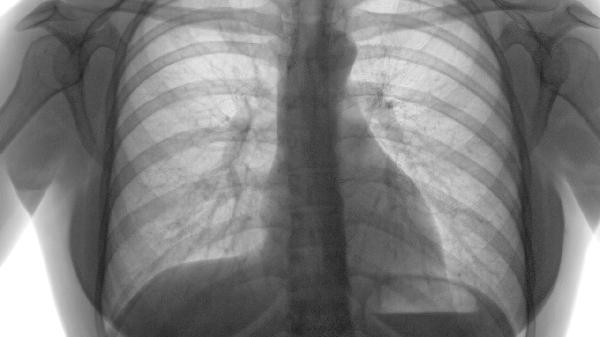

桶状胸是胸廓前后径增大的体征,由长期肺过度充气导致。轻微肺气肿患者肺组织破坏程度较轻,多数尚未形成典型桶状胸,但随病情进展可能逐渐显现。早期肺气肿胸部X线或CT可能仅显示肺透亮度轻度增加。